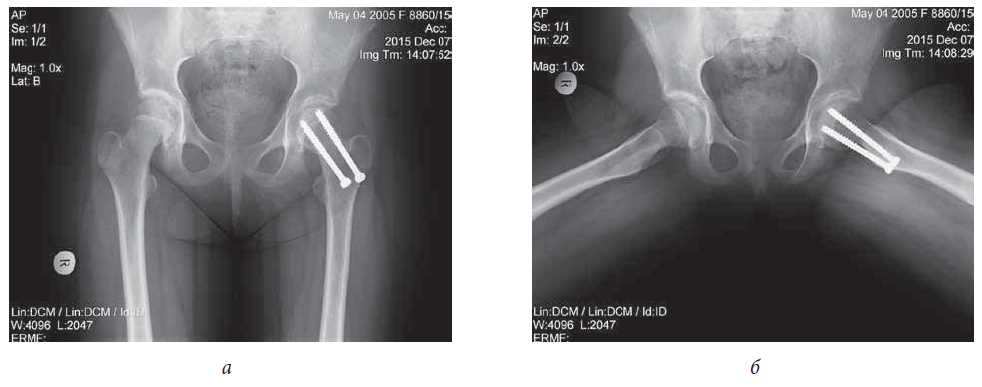

Surgical treatment was performed for the partial removal of surgical hardware, followed by the closed reposition of the femoral neck fragments with DHS plate fixation (Fig. 7, a, b). Given the patient’s history, an open repositioning with complete removal of the surgical hardware was not an option because of the increased risk of aseptic necrosis of the femoral head that could result from additional trauma to nutrient vessels of the femoral epiphysis in the course of capsulotomy and bone fragments mobilization.

Fig. 7. Patient M., age 14: a, b - radiograph and CT of hip joints after repeated closed repositioning, partial removal of metal structures and osteosynthesis by a dynamic femoral screw (DHS) in a direct projection: restoration of angular values corresponding to the contralateral limb